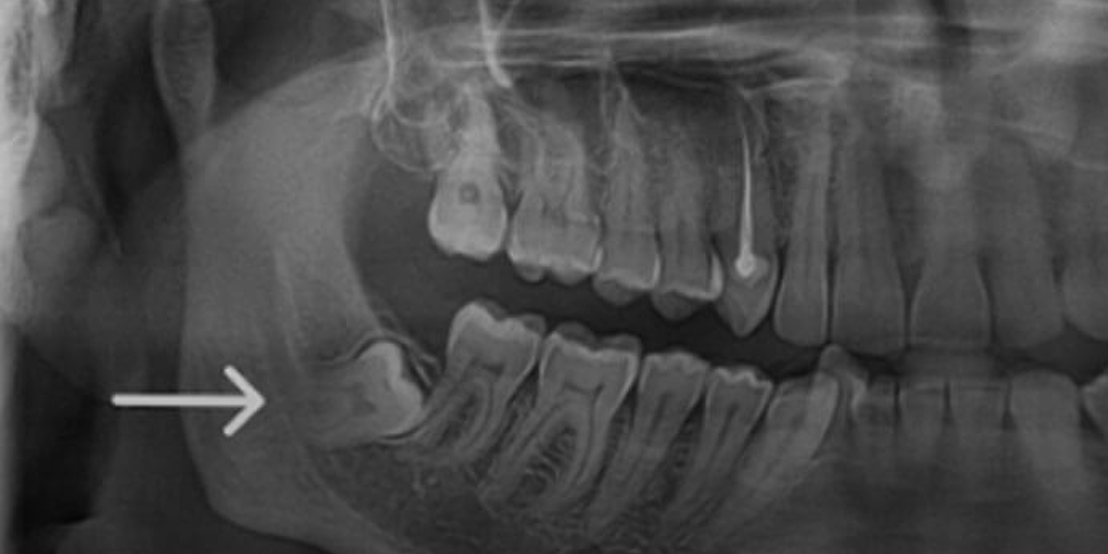

Surgical Extraction

As part of the best wisdom tooth extraction Dubai options, it ensures optimal care, comfort, and long-term oral health.